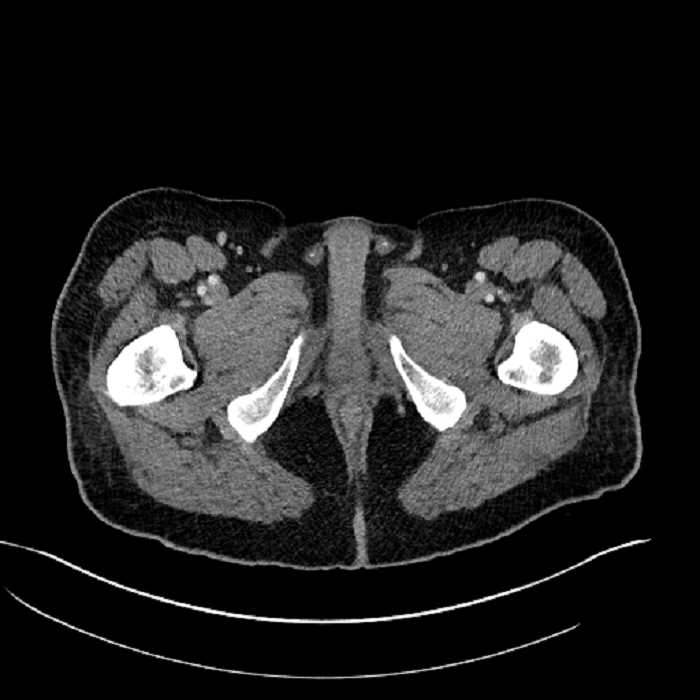

Age: 63

Sex: Male

Indication: Abdominal pain

• Large fluid density structure in hepatic segments 7 and 8 measuring 10 x 7 x 7 cm with internal septation and circumferential ill-defined low density compatible with edema

• Peripherally enhancing subcapsular collections along the anterior margin of the left hepatic lobe measuring 3 x 1 cm and 2 x 1 cm

• Clearly marginated fluid density structure in segment 7 and several other scattered tiny hypodensities, which likely represent cysts

• High grade stenosis of the left common iliac artery, with the left internal and external iliac arteries remaining patent

• Hepatic abscess

Acute sigmoid diverticulitis complicated by a small contained perforation and a large abscess in the right hepatic lobe. Additional small subcapsular abscesses along the anterior margin of the left hepatic lobe.

Additionally, loss of the normal fat plane between the peridiverticular collection and adjacent thickened loops of small bowel raises the potential for an enterocolonic fistula.

High grade stenosis of the left common iliac artery. The left external and internal iliac arteries are patent.

• The classic CT imaging appearance is a double target sign with internal low density surrounded by an internal enhancing rim (capsule) and a low density external rim (edema)

Hepatic abscess showing the double target sign with low density internally surrounded by a thin inner enhancing rim (red arrow) and ill-defined outer low density rim (yellow arrow). Blue arrow indicates an internal septation. Red arrows: additional smaller subcapsular abscesses. Red arrow: focal contained perforation associated with diverticulitis.